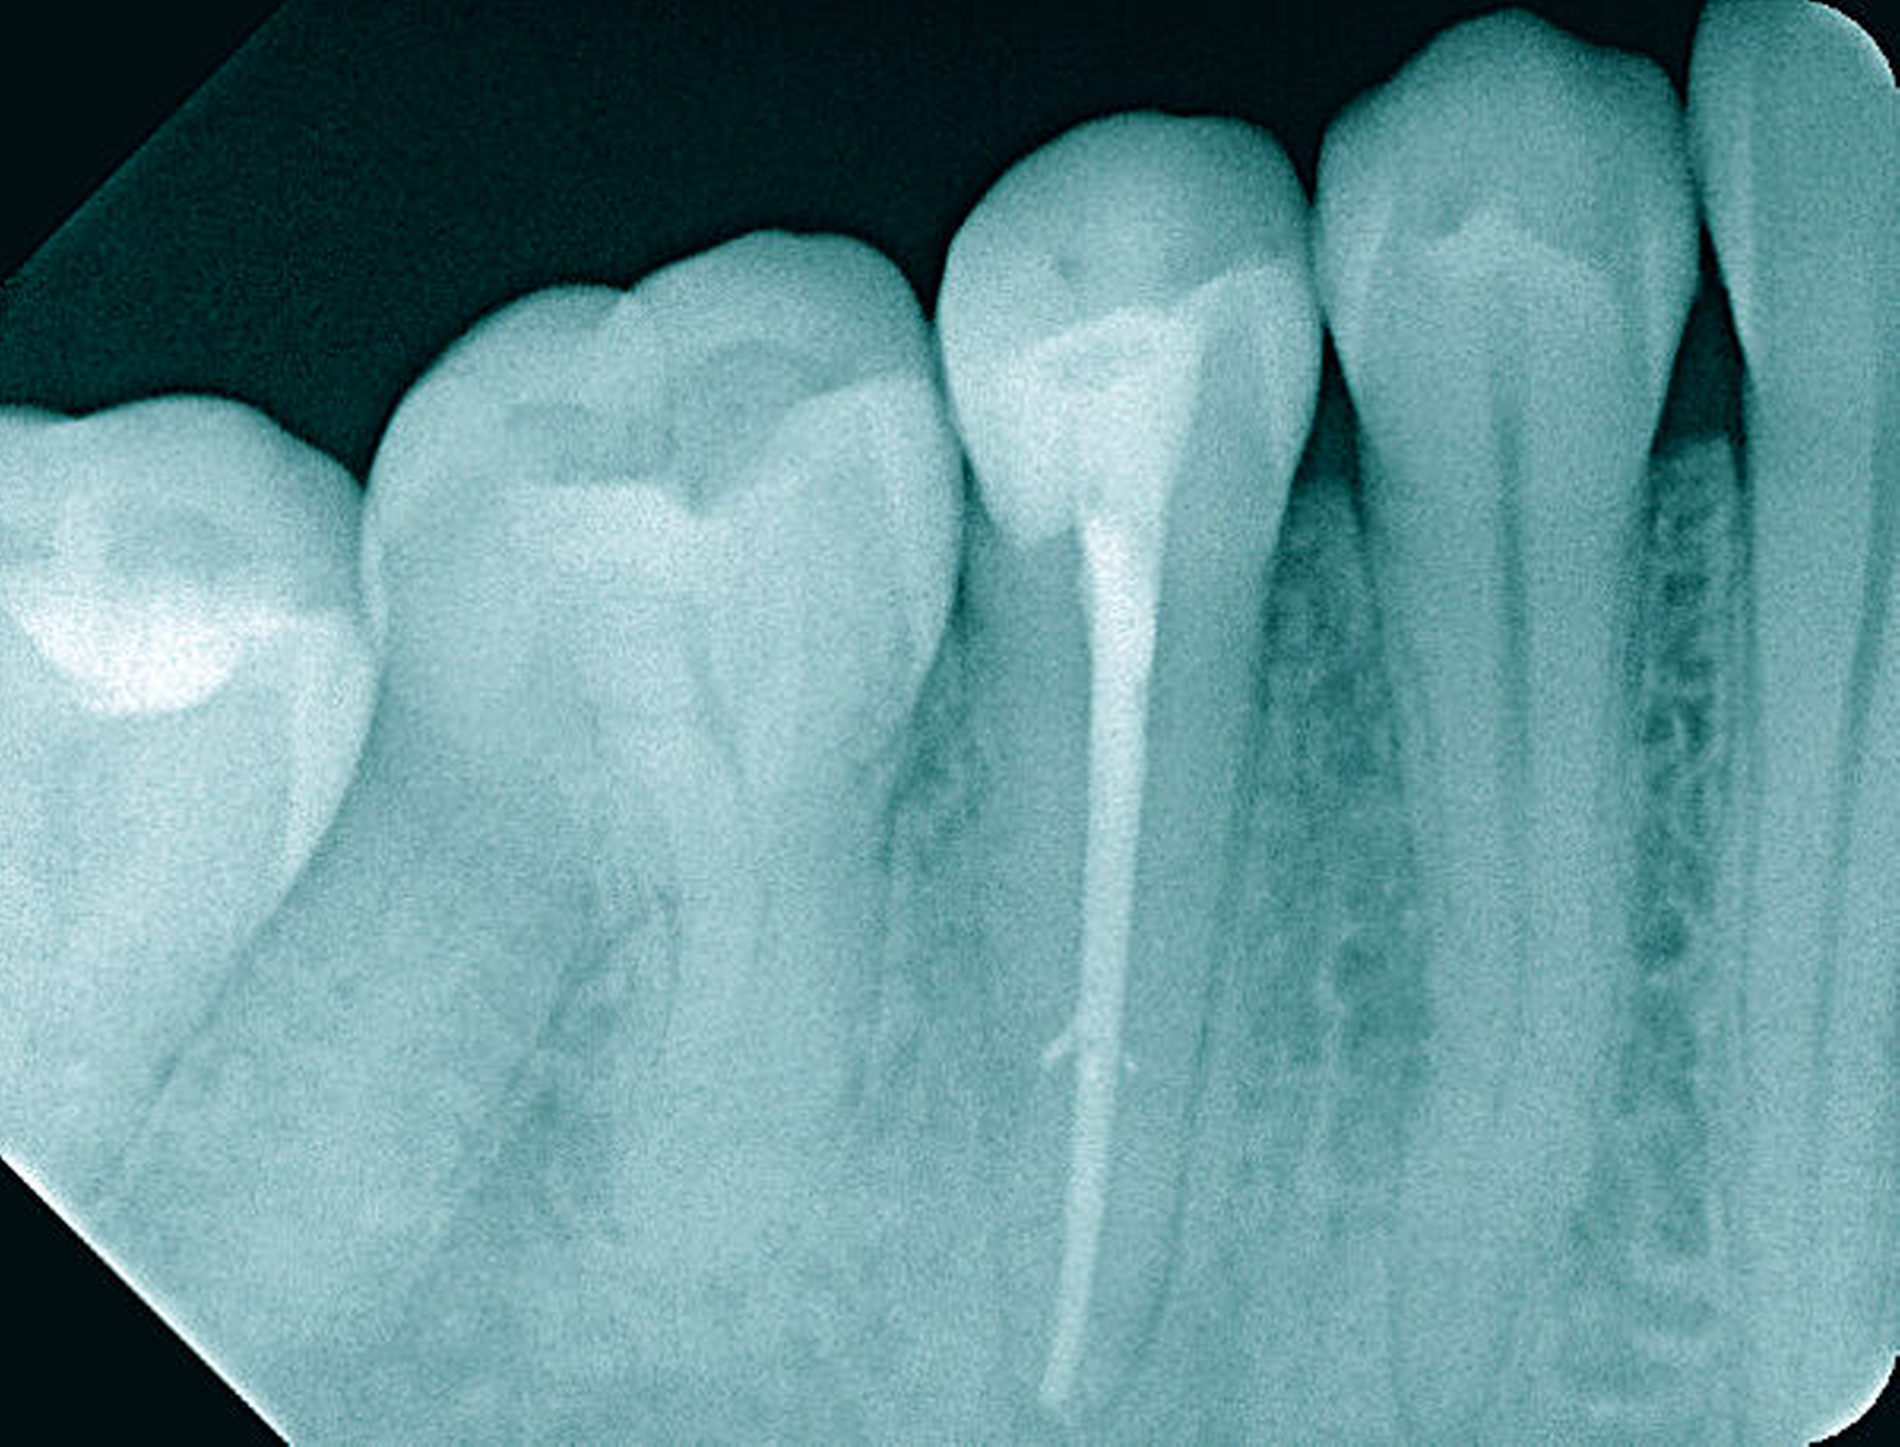

Nach klinischer und radiologischer Untersuchung wurde am Zahn 45 eine irreversible Pulpitis diagnostiziert. Anamnestisch konnten Komplikationen ausgeschlossen werden. Die klinischen Befunde waren eindeutig auf den Zahn 45 lokalisierbar. Der auf der Röntgenaufnahme geradlinige und vollständig bis zum Apex verfolgbare Wurzelkanal ließ einen normalen Schwierigkeitsgrad bei sehr guter Prognose erwarten (Abbildung 11a).

Die Therapie erfolgte unter Verwendung von Kofferdam und Lupenbrille. Die mechanische Erweiterung des Wurzelkanals und die Wurzelkanalfüllung erfolgten nach elektrometrischer und röntgenologischer Arbeitslängenbestimmung (Abbildungen 11b und 11c). Nach Abschluss der Wurzelkanalbehandlung war die Patientin beschwerdefrei.